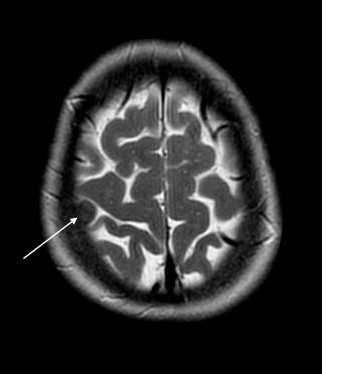

(б) МРТ, постконтрастное Т1-ВИ, корональный срез: определяются протяженное контрастирование «серпантинного» характера утолщенной мягкой мозговой оболочки (пиальный ангиоматоз) и увеличение субарахноидального пространства над правым большим полушарием головного мозга. Очевидна выраженная правосторонняя гемиатрофия головного мозга. (а) МРТ, постконтрастное Т1-ВИ, аксиальный срез: определяется классический синдром Стерджа-Вебера (ССВ) в виде атрофии правого большого полушария, увеличения размеров ипсилатерального сосудистого сплетения и распространенного пиального ангиоматоза, покрывающего практически всю поверхность полушария.

(б) МРТ, постконтрастное Т1-ВИ, более краниальный аксиальный срез: у того же пациента определяются схожие изменения. На данном изображении в субарахноидальном пространстве визуализируется скопление расширенных сосудов.